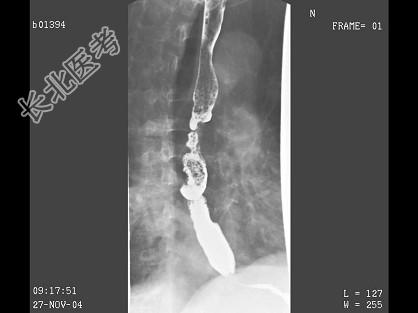

- 单项选择题男,71岁, 脾大、腹水、肝管结石2年,结合图像, 最可能的诊断为 ( )

E、食管癌